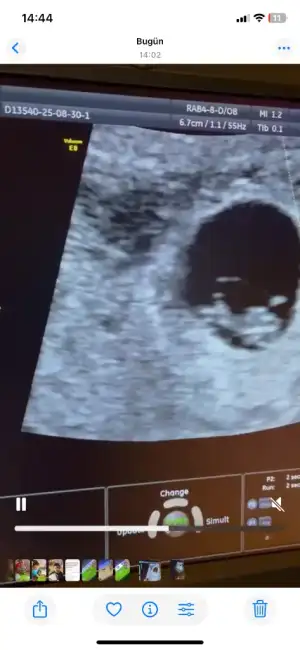

Arkadaşlar merhaba daha önce burada ultrason fotoğrafına bakıp cinsiyet tahmin edenleri görmüştüm benim içinde bi heyecan olur:) var mıdır tahmininiz normalde 12+4 üm ama ultrasonda 13 haftalık görünüyor.

Benimde 13+1 de karından ultrason ile bakıldı tahmin de bulunabilir misiniz 🙏